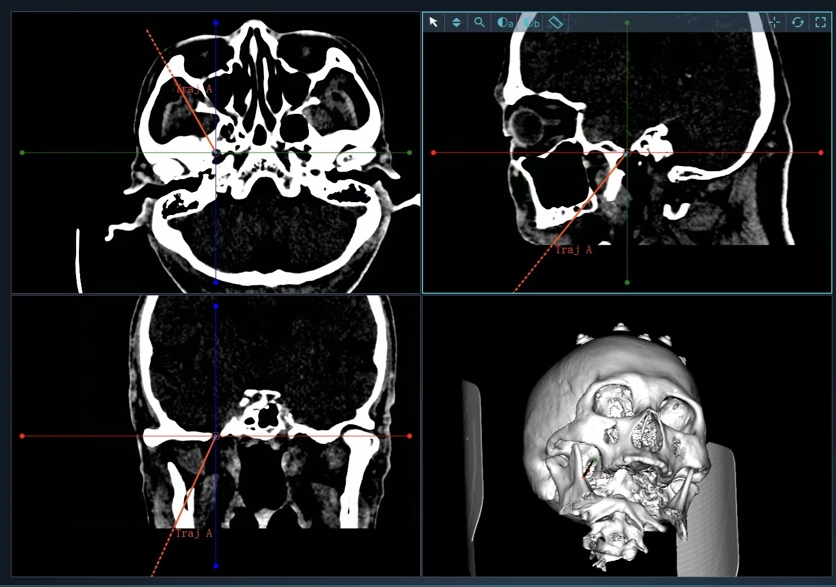

图3 术中在机器人辅助下穿刺并置入球囊

图4 术中C型臂透视显示:球囊成形好,压迫满意

但该患者手术需要精确的三维定位,术中需把穿刺针准确穿入皮下约8cm深、直径仅为3mm左右的卵圆孔,传统方法只能在C型臂引导下徒手穿刺,一次性穿刺成功率低。如何高效率穿刺成功,从而减少患者术中风险成为了迟令懿团队亟待解决的问题。在神经外科副主任李卫国的指导下,迟令懿采用机器人辅助立体定向下穿刺。术前验证误差仅为0.3mm,术中仅用10秒钟即完成了穿刺操作,避免了反复穿刺导致的血管、组织损伤,减少了C型臂透视的次数,降低了手术风险和并发症。术后,患者面部疼痛即刻消失,1天后顺利出院。